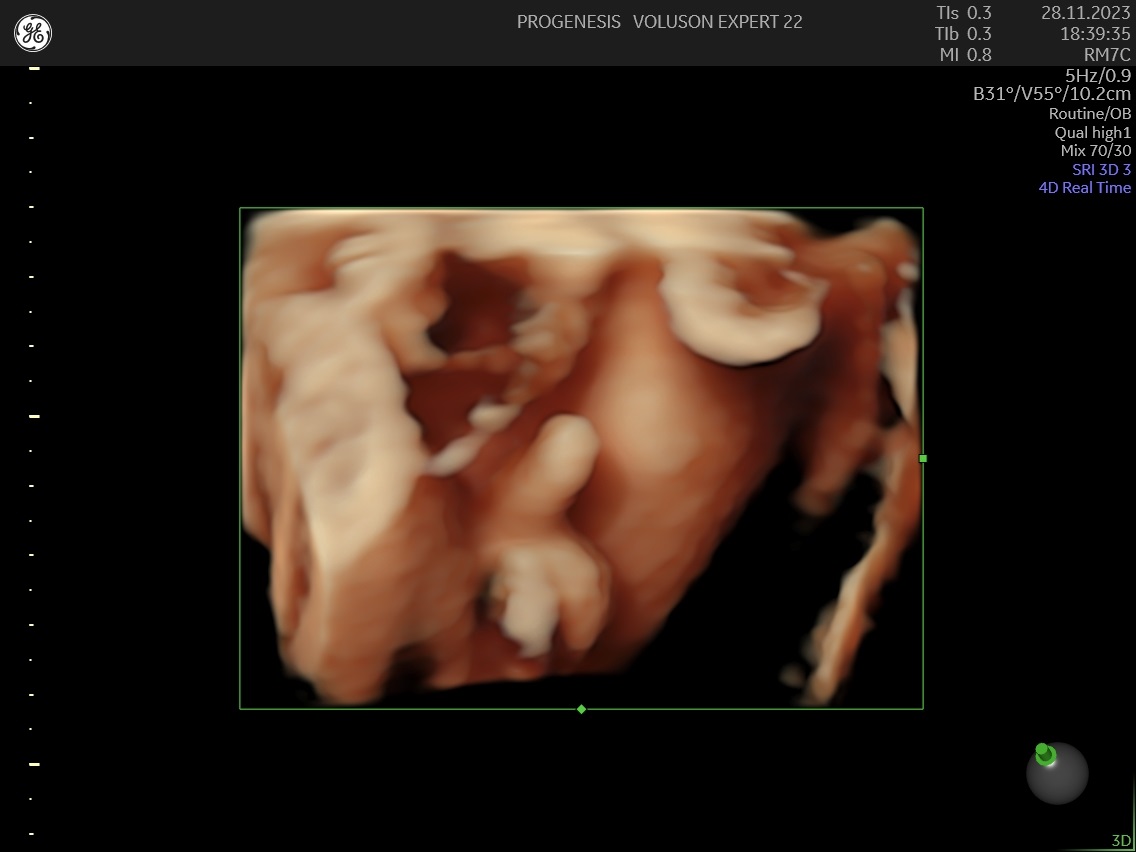

Το 3D/4D LIVE είναι μια νέα τεχνολογία υπερήχων που δημιουργεί εικόνες του εμβρύου σε τρισδιάστατο ή τετραδιάστατο χώρο. Οι εικόνες αυτές είναι πιο ρεαλιστικές από τις παραδοσιακές εικόνες υπερήχων και δίνουν στους γονείς μια πιο ολοκληρωμένη εικόνα του μωρού τους.

Σε πιθανά ανατομικά προβλήματα του εμβρύου μπορούν να βοηθήσουν στην κατανόησή τους από τους γονείς.

Ωστόσο, οι εικόνες 3D/4D LIVE δεν μπορούν να αντικαταστήσουν τις παραδοσιακές εξετάσεις υπερήχων.